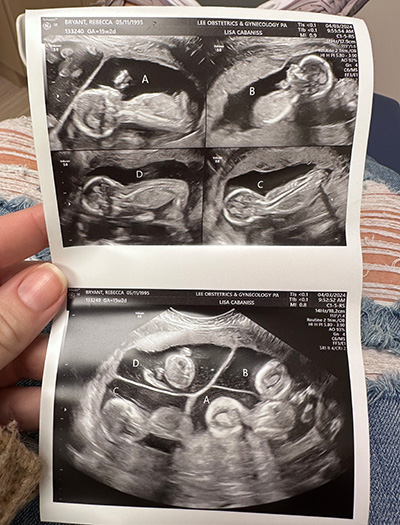

Ultrasound picture of Becca Bryant's trichorionic quadra-amniotic pregnancy, meaning there were four babies and four sacs but only three placentas.Becca had a trichorionic quadra-amniotic pregnancy, meaning there were four babies and four sacs but only three placentas. (Photography provided by Becca Bryant)“The ultrasound tech started moving the machine around, and I started to notice one big spot and two smaller ones,” Lavareis said. “The next thing I know, she’s counting — 1 … 2 … 3 … 4!”

Multiple pregnancies are rare, with twins occurring in one in 80 and quadruplets occurring in one in 700,000. Becca had a trichorionic quadra-amniotic pregnancy, meaning there were four babies and four sacs but only three placentas.

“The odds of this specific type of quads are around one in 7 million,” said Ayodeji Sanusi, M.D., Becca’s maternal-fetal medicine physician at UAB. “Three eggs were fertilized; but one split, making two of the babies identical and two fraternal. It also added on to the complex and high-risk nature of her pregnancy.”